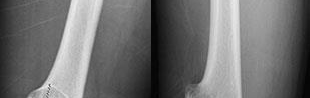

Question 16

A 32-year-old male develops extreme pain out of proportion, pain with passive stretch, and tense compartments following a closed tibial shaft fracture. Which of the following best describes the fundamental pathophysiologic mechanism leading to cellular hypoxia and tissue death in acute compartment syndrome?

Explanation

The pathophysiology of compartment syndrome is driven by an increase in interstitial tissue pressure within a closed non-yielding fascial space. As tissue pressure rises, it quickly surpasses the low capillary venous pressure, severely impairing venous outflow. This leads to a decreased arteriovenous (AV) pressure gradient, resulting in diminished local capillary blood flow, capillary collapse, ischemia, and subsequent muscle/nerve necrosis. Arterial inflow is typically maintained until very late, which is why pulses are usually palpable even in established compartment syndrome.